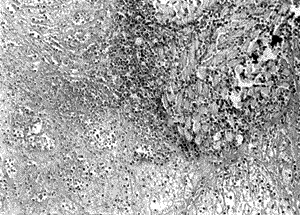

懶惰性白細胞顯微像診斷檢查